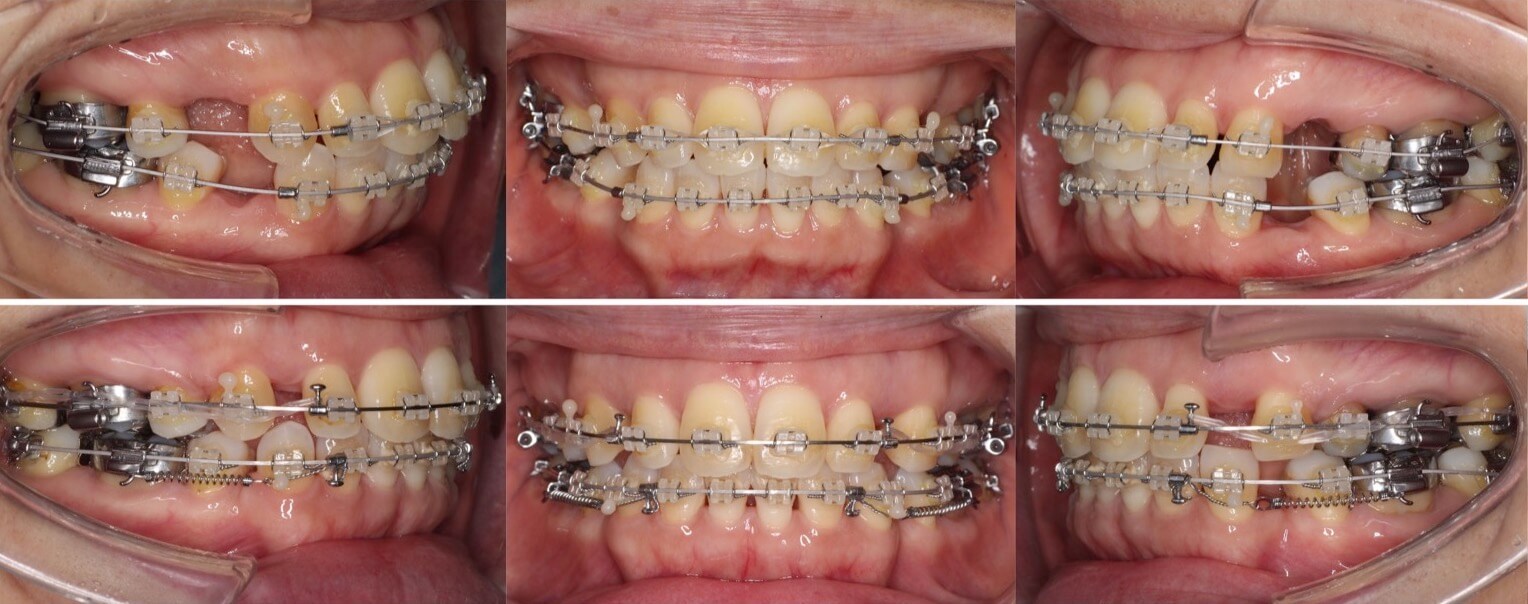

43歳女性・唇側矯正装置・抜歯

ミドルエイジの矯正治療で抜歯方針を選択する場合は、細心の注意を払います。これは、前歯が後方に引き下がりすぎる可能性があるからです。事前に横顔のシミュレーションを確認していただき、ほうれい線が深くなるなどのリスクも承諾の上、治療を開始しました。治療後はバランスの良い横顔になりました。

<症例概要>

主訴:口元の突出

年齢・性別:43歳女性

住まい:千葉県八千代市

症状:上下顎前歯唇側傾斜・正中離開

治療方針:上下左右4番(計4本)

治療装置:唇側矯正装置

固定装置:ナンスホールディングアーチ

治療期間:2年9か月

リテーナー:上下フィックス+プレートタイプ

治療費用:968,000(税込)

代表的副作用:痛み・治療後の後戻り・歯根吸収・歯髄壊死・歯肉退縮

▶︎その他の副作用